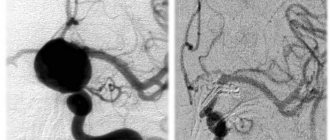

• Ангиография. Можно получить основную информацию о расположении, форме и размере аневризмы мозга.

Во время эндоваскулярной окклюзии аневризмы нейрохирург проводит блокировку просвета расширенного сосуда специальным имплантом. Операция применяется при невозможности провести клипирование, например, когда аневризма имеет веретенообразную форму. Во время хирургического вмешательства через бедренную артерию потом ангиграфическим контролем специалист вводит баллон-катетер. Он закрывает просвет аневризмы. Также можно использовать микроспираль для проведения тромбирования. Выбор остается за лечащим врачом. Микроспираль в полости пораженного сосудистого участка образует тромбы, которые закупоривают просвет сосуда и выключают аневризмы из кровообращения.

В 2 случаях в связи с сохраняющейся симптоматикой был выполнен второй этап оперативного вмешательства, заключавшийся в декомпрессивной трепанации задней черепной ямки и удалении мешка аневризмы, оказывающего компрессионное воздействие на ствол головного мозга (рис. 2).

Рис. 2. Гигантская аневризма правой верхней мозжечковой артерии. а, б, в — МРТ в коронарной, сагиттальной и аксиальной проекциях, режим Т1 В.И. Визуализируется мешок гигантской аневризмы, грубо сдавливающий ствол головного мозга; г — СКТ-ангиография, белой стрелкой указана заполняющаяся часть аневризмы; д — этап операции удаления тромботических масс из полости аневризмы. Интраоперационное фото. АА — мешок аневризмы, Cer — мозжечок; е — СКТ головного мозга после операции, отмечается значительное уменьшение размеров аневризматического мешка с уменьшением компрессии ствола.